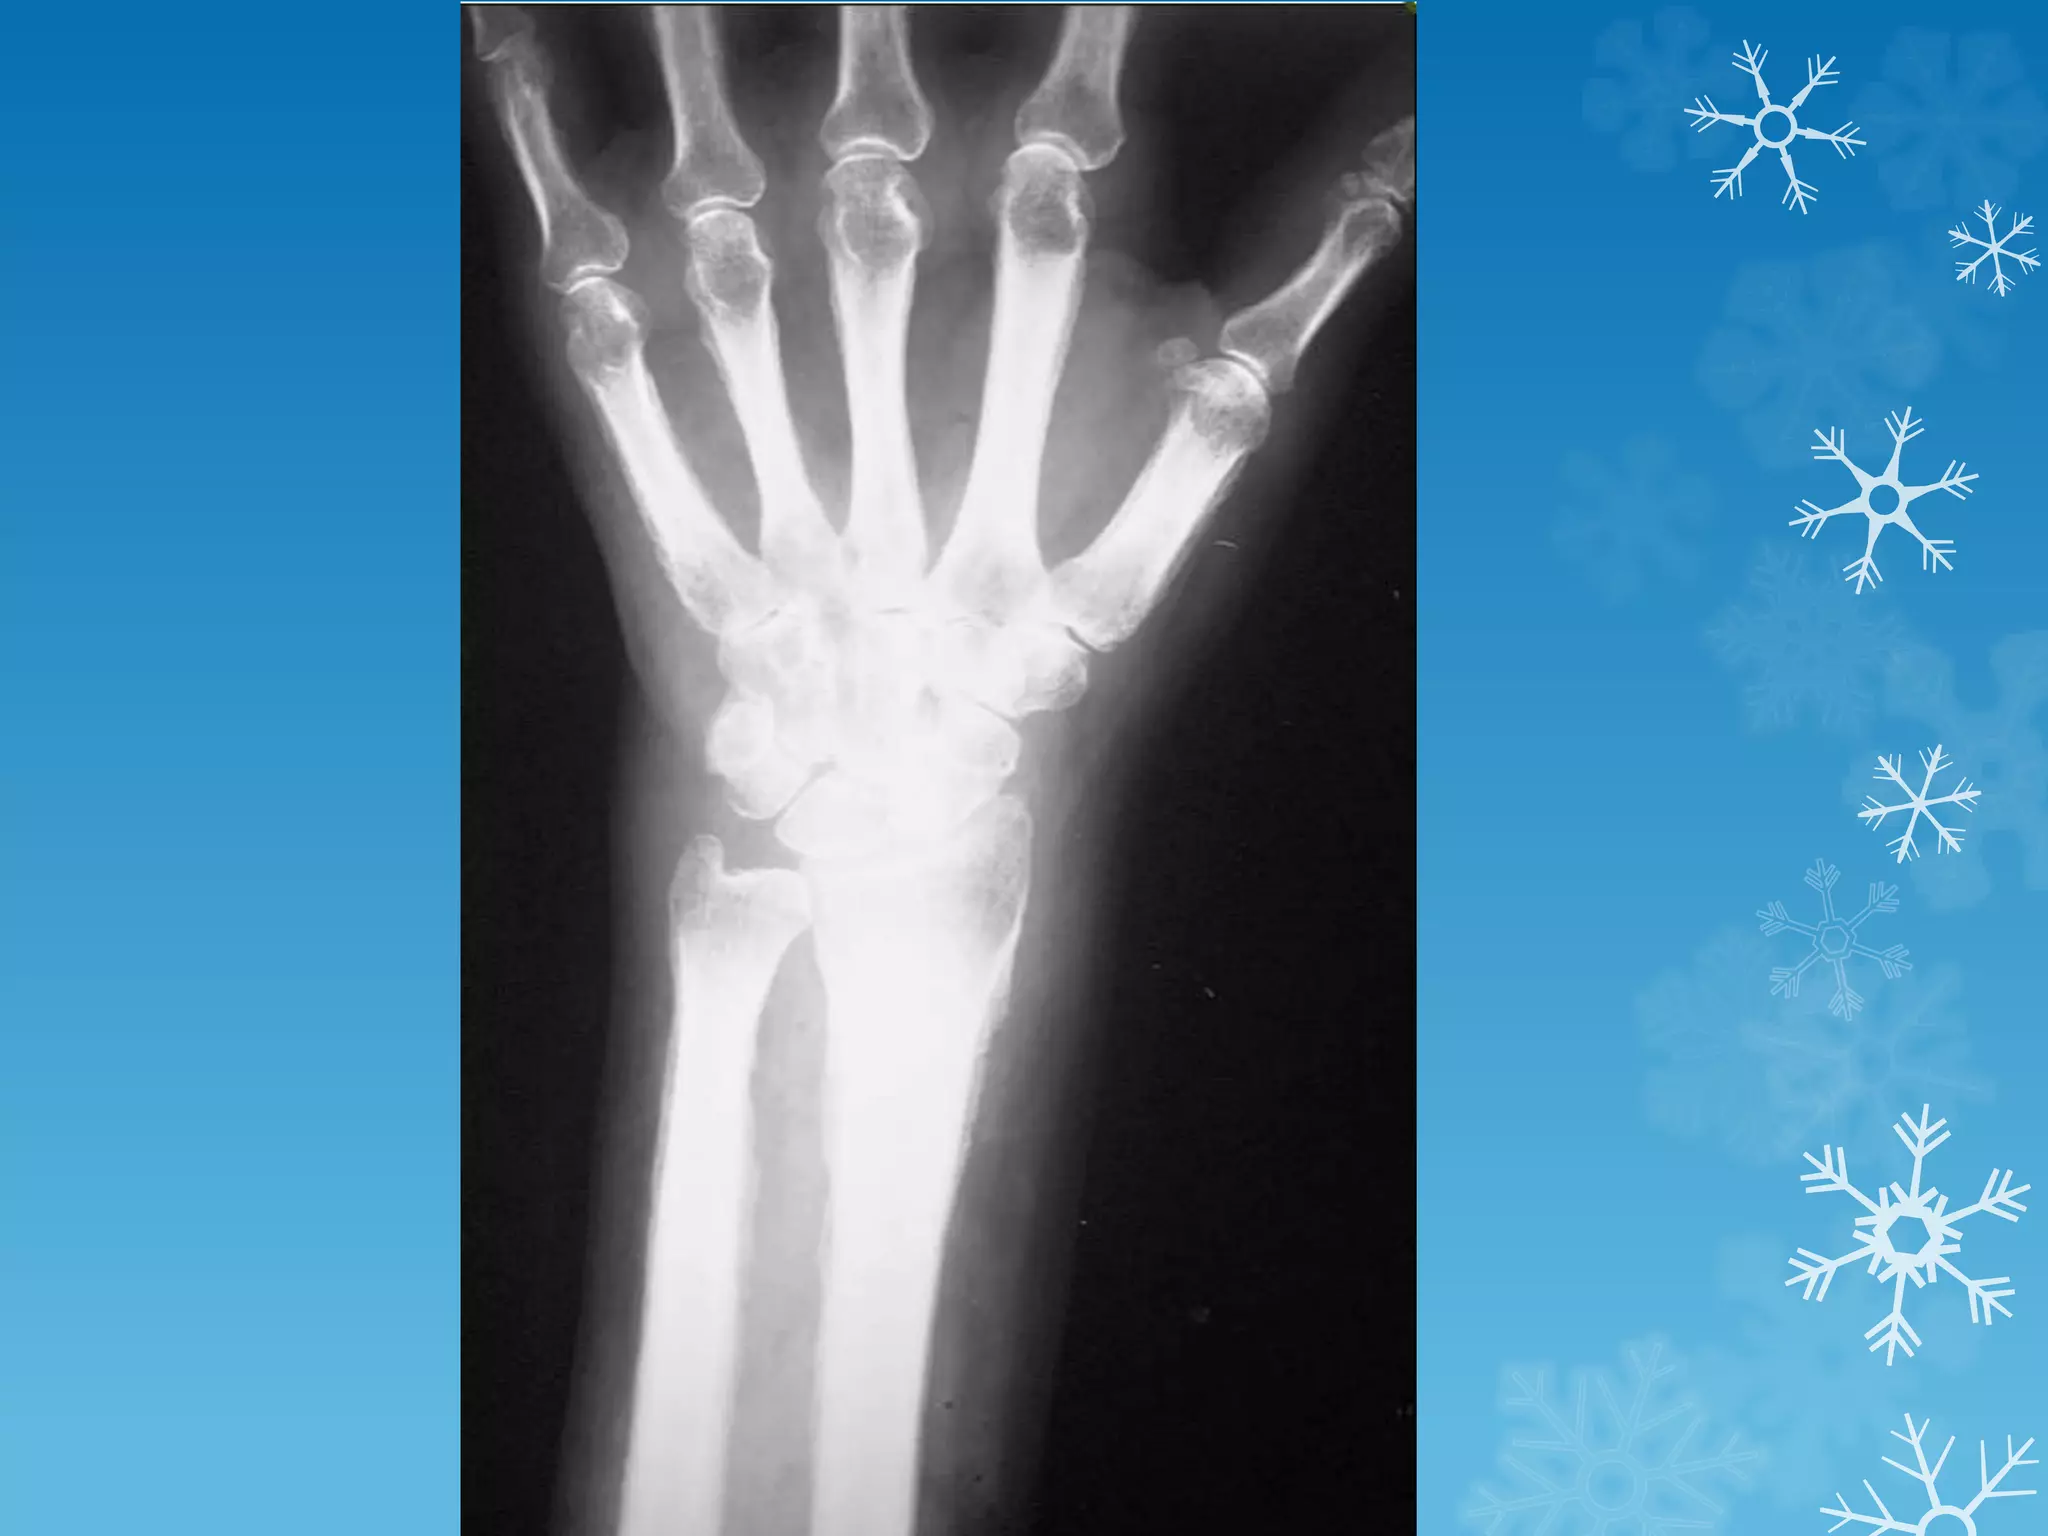

Anteroposterior view of the hand in this patient with sarcoid

demonstrates classic changes of bony involvement with this

granulomatous process.

Note the lacelike pattern of destruction, which is seen most

prominently in the proximal phalanges and in the distal third

phalanx.

Soft tissue swelling and some areas of severe bony dissolution

are also noted, which occur in more advanced patterns of

sarcoid.

These changes are typically limited to the hands but can rarely

occur in other parts of the skeleton.